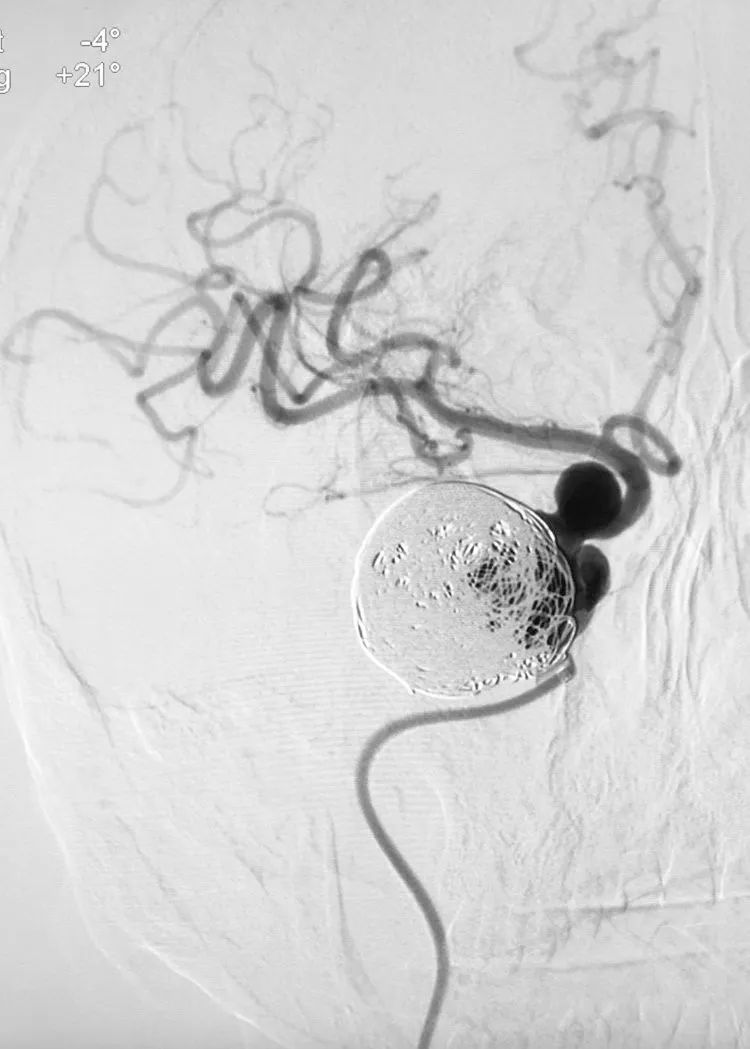

完全释放Tubridge®密网支架。

术后右颈内动脉正侧位造影显示:右大脑前动脉不显影,考虑为血流动力学因素所致。

转行左颈内动脉正位造影证实前交通动脉开放。

左侧颈内动脉床突段及左侧大脑中动脉M1段也有多发动脉瘤,等待三期治疗。